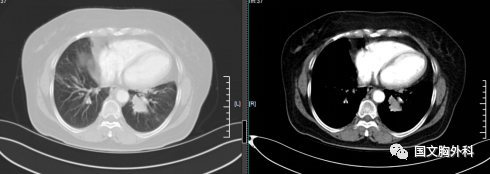

因病灶位置關(guān)系經(jīng)過支氣管鏡檢查未能明確病理,病灶包裹著血管CT穿刺風(fēng)險(xiǎn)巨大。

經(jīng)國文醫(yī)院MDT,全院專家會(huì)診,先行手術(shù)治療。